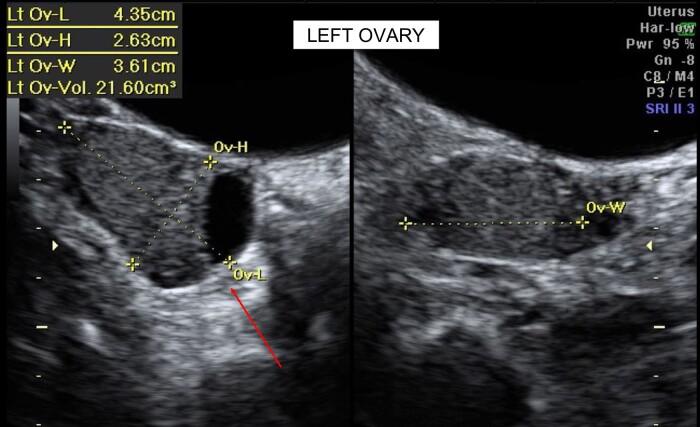

Virilizing ovarian tumors are rare but a clinically important diagnosis in a patient presenting with hyperandrogenism. Workup of hyperandrogenism is challenging with a broad range of differentials, including adrenal and ovarian pathology, tumoral or nontumoral in nature. Baseline follicular-phase 17-hydroxyprogesterone (17OHP) measurement is part of the investigation algorithm, and elevated levels are often associated with nonclassic congenital adrenal hyperplasia (NCCAH), which can have its first presentation in adolescence or adulthood. This case describes a young adult woman of reproductive age presenting with menstrual irregularity, raised testosterone, and 17OHP. After extensive workup and serial follow-up, she was found to have a Sertoli-Leydig cell tumor of the left ovary and underwent successful laparoscopic salpingo-oophorectomy with normalization of her menstrual irregularity and biochemical resolution of her testosterone and 17OHP levels.

男性化卵巢肿瘤罕见,但对于出现高雄激素血症的患者来说是一个具有临床重要性的诊断。高雄激素血症的检查颇具挑战性,鉴别诊断范围广泛,包括肾上腺和卵巢病变,性质上有肿瘤性或非肿瘤性。基础卵泡期17-羟孕酮(17OHP)测量是检查算法的一部分,其水平升高常与非经典型先天性肾上腺皮质增生症(NCCAH)相关,该病可在青春期或成年期首次出现。本病例描述了一名育龄期年轻成年女性,出现月经不规律、睾酮升高和17OHP升高。经过广泛检查和系列随访,发现她左卵巢有一个支持-间质细胞瘤,并接受了成功的腹腔镜输卵管卵巢切除术,月经不规律得以恢复正常,睾酮和17OHP水平在生化方面也恢复正常。